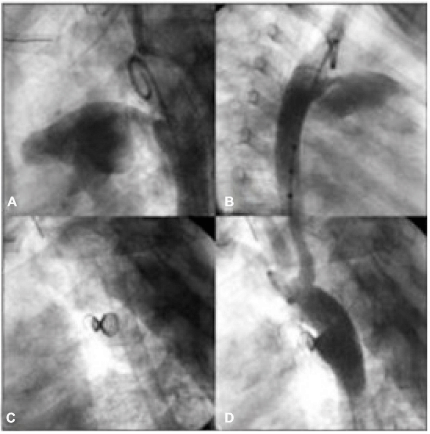

Na figura abaixo, observa-se uma oclusão de ducto arterioso. A e B: A ortografias demonstrando canal arterial tipo A, com diâmetro mínimo de 3,7 mm (milímetros) e ampola aórtica de 11 mm (milímetros); C: Dispositivo liberado com morfologia em duplo cone; D: Aortografia final com mínimo fluxo residual.

Qual alternativa apresenta o dispositivo de oclusão utilizado.